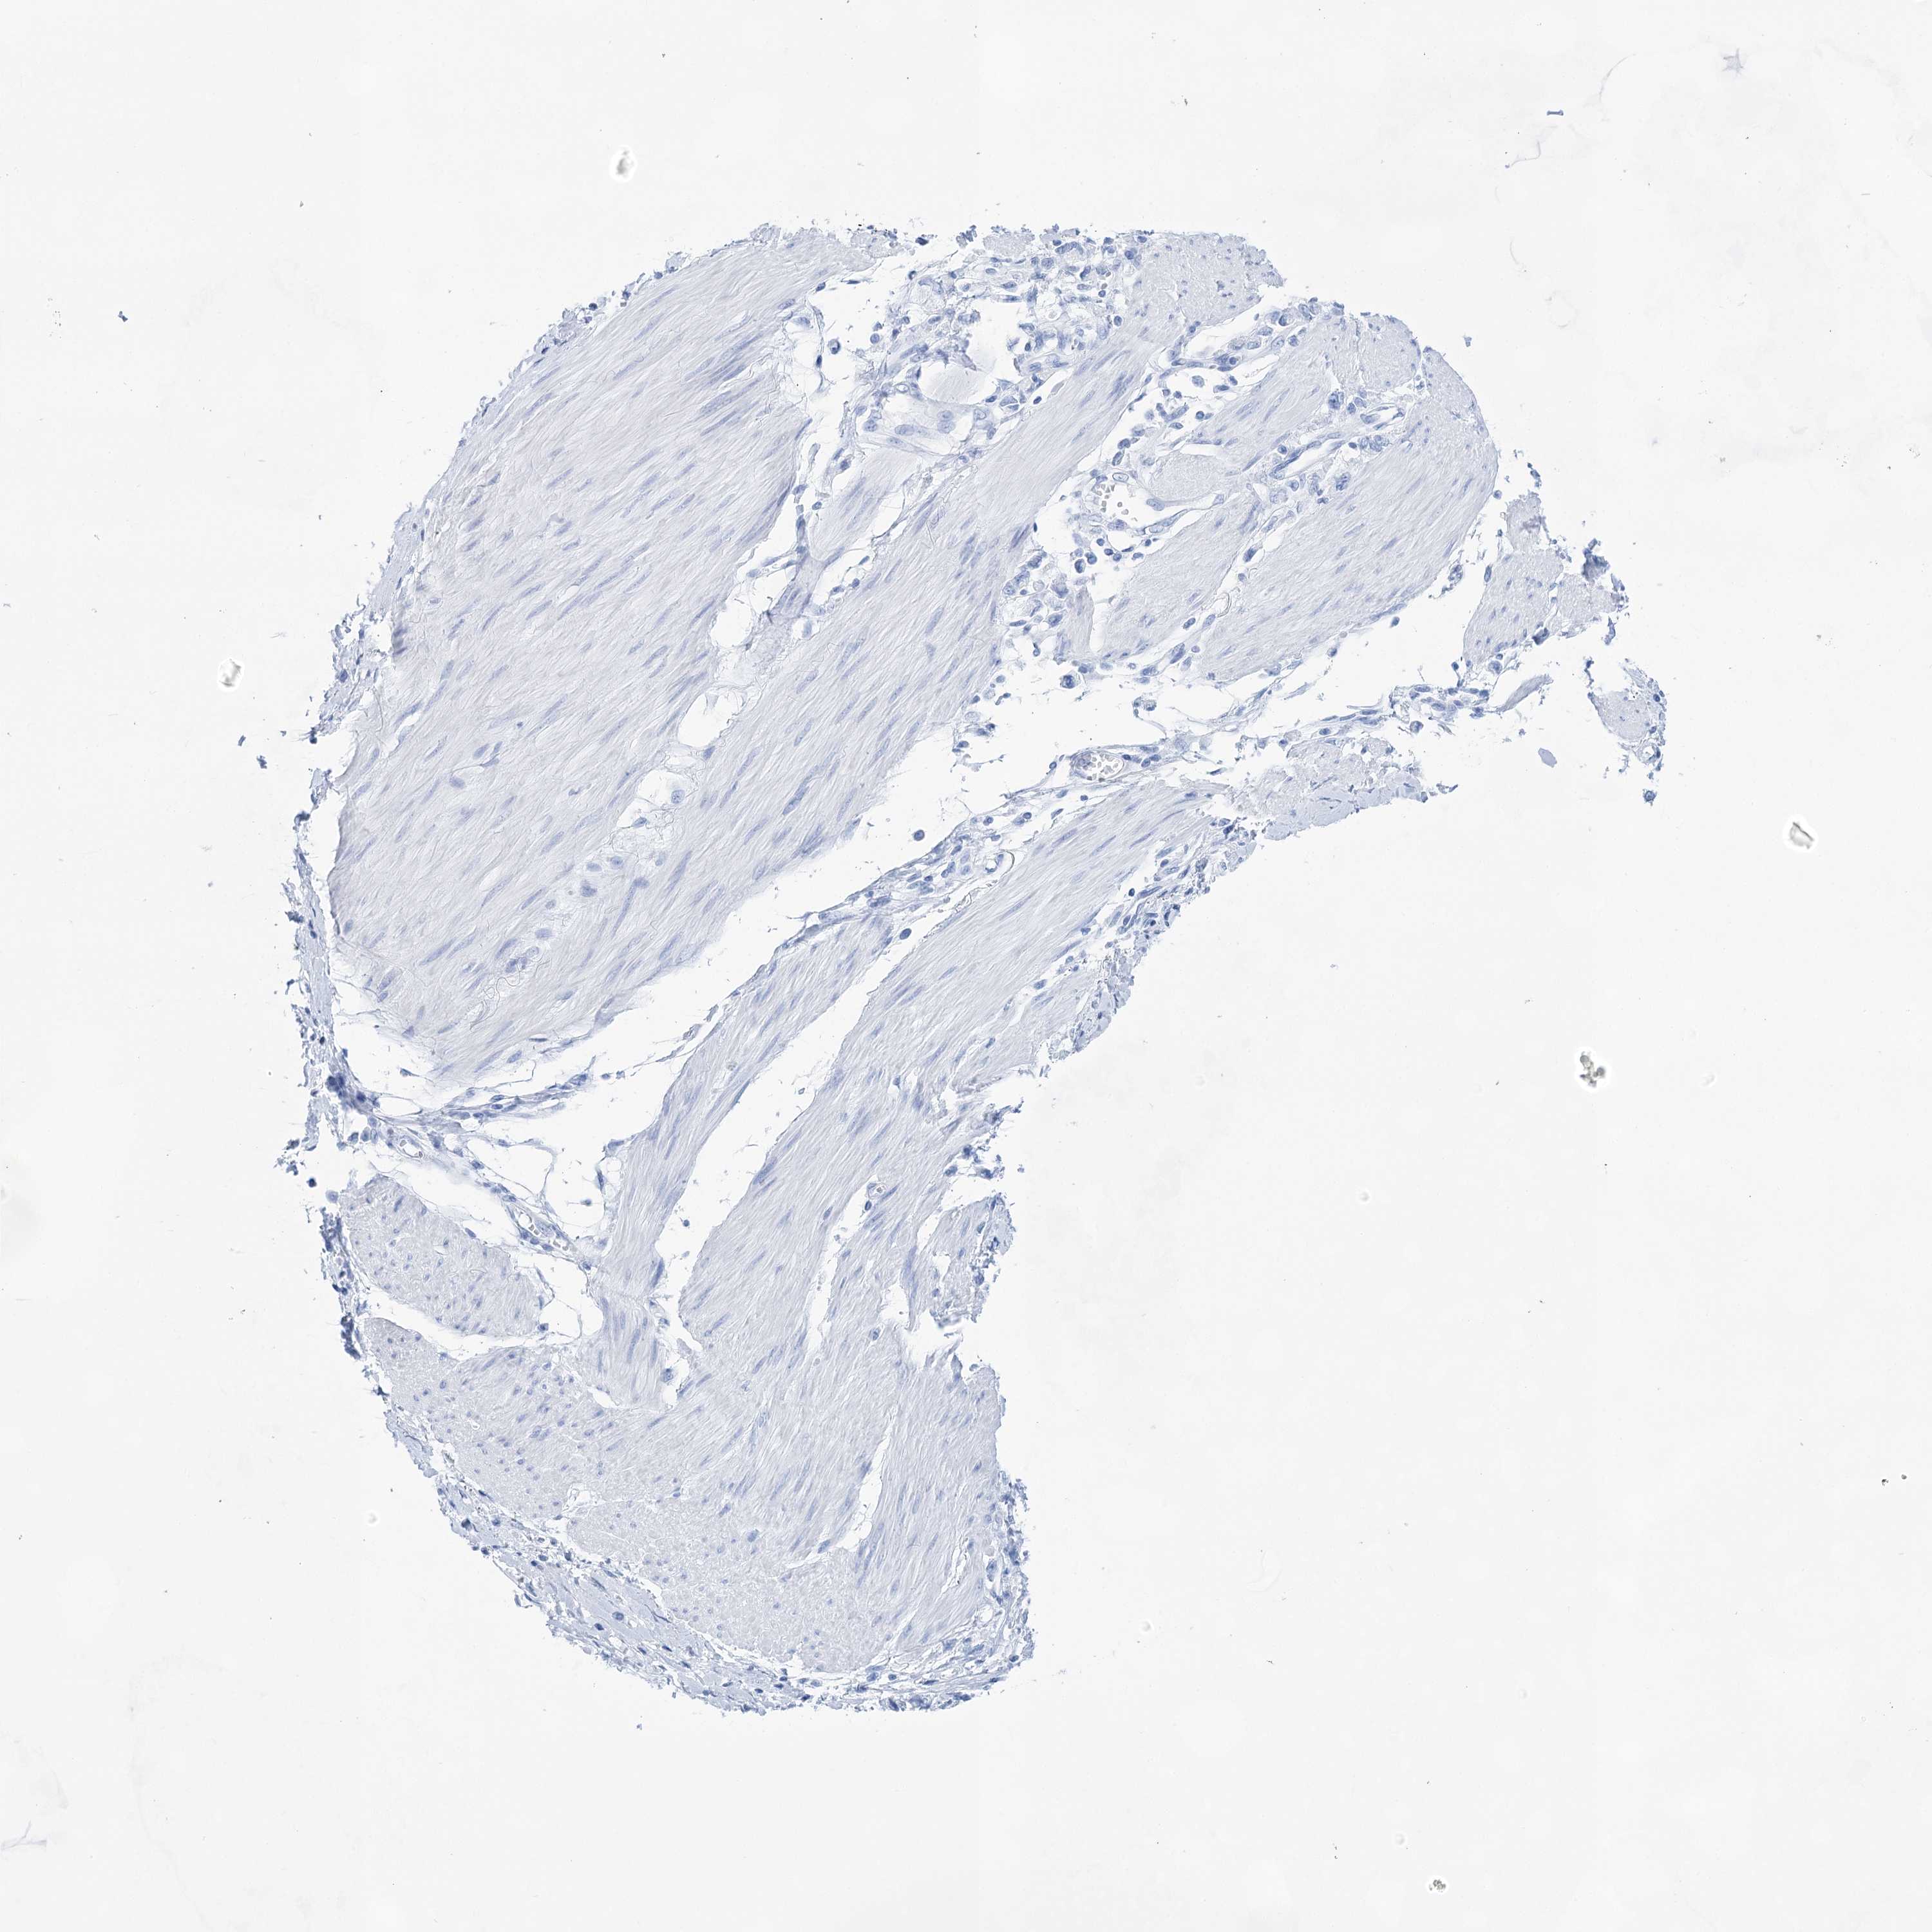

STOMACH CANCER - Protein expressioni

A mouse-over function shows sample information and annotation data. Click on an image to view it in a full screen mode. Samples can be filtered based on level of antibody staining by selecting one or several of the following categories: high, medium, low and not detected. The assay and annotation is described here.

Note that samples used for immunohistochemistry by the Human Protein Atlas do not correspond to samples in the TCGA dataset.

Antibody stainingi

Antibody staining in the annotated cell types in the current human tissue is reported as not detected, low, medium, or high, based on conventional immunohistochemistry profiling in selected tissues. This score is based on the combination of the staining intensity and fraction of stained cells.

Each image is clickable and will lead to virtual microscopy that enables deeper exploration of all samples and also displays staining intensity scores, fraction scores and subcellular localization as well as patient and tissue information for each sample.

Antibody HPA029855

Antibody HPA029856

Antibody CAB026343

Staining

High

Medium

Low

Not detected

Intensity

Strong

Moderate

Weak

Negative

Quantity

>75%

75%-25%

<25%

None

Location

Nuclear

Cytoplasmic/membranous

Cytoplasmic/membranous,nuclear

Adenocarcinoma, NOS